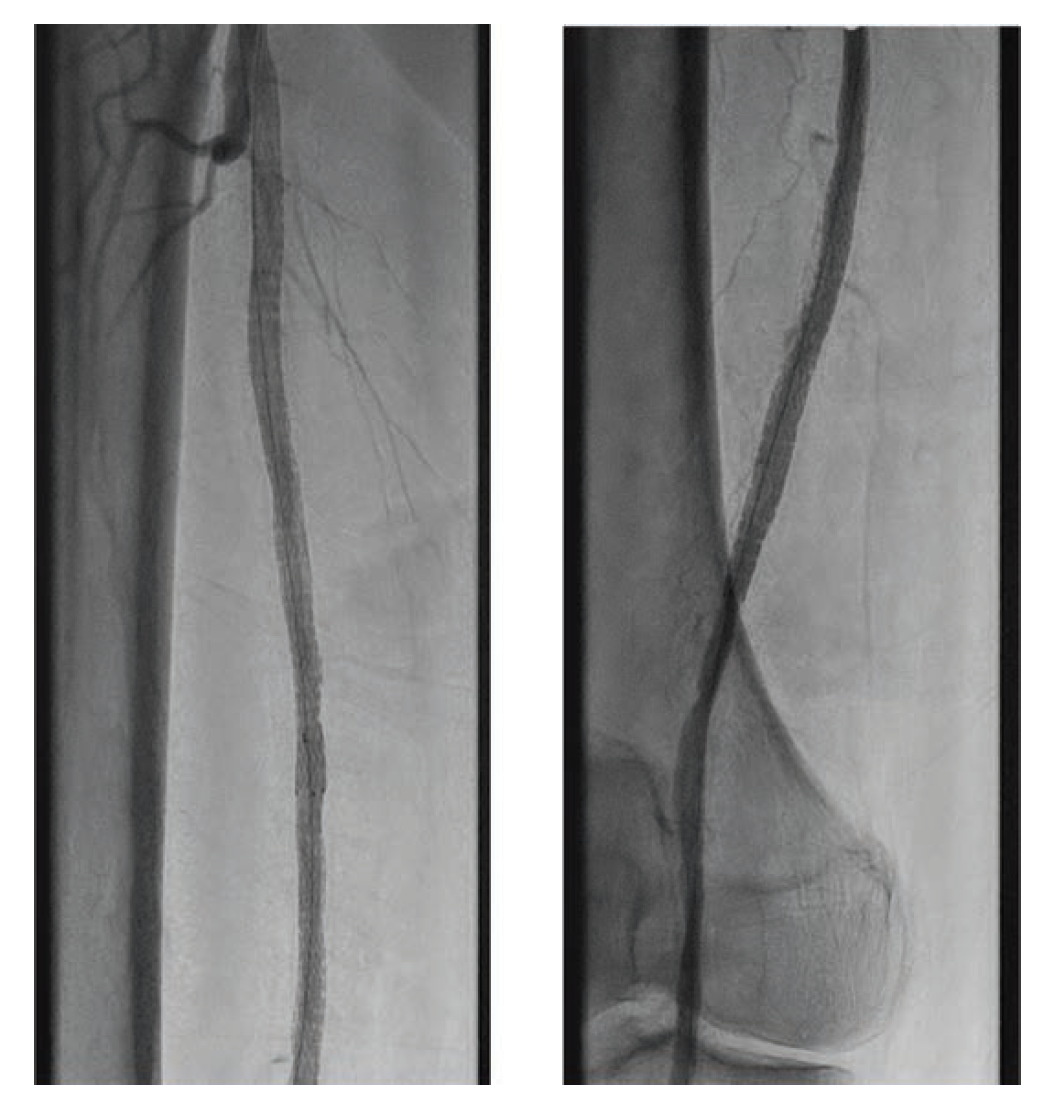

A 70-year-old man was referred for consideration of right lower extremity (RLE) intervention after initially presenting with resting ischemic pain and early tissue necrosis of the metatarsals, consistent with critical RLE ischemia. The patient was taken to the catheterization lab, where contralateral left common femoral artery (CFA) access was gained using a Micropuncture needle (Cook Medical) under ultrasound guidance. A 6F, 11 cm arterial sheath was placed into the artery over a guidewire. The right common iliac artery was engaged using a 5F internal mammary artery catheter; a 0.035" stiff-angled Glidewire (Terumo Interventional Systems) was then advanced to the right CFA. Peripheral angiography of the RLE was performed, demonstrating a total occlusion of the superficial femoral artery (SFA) as well as total occlusion of the popliteal artery and all three infrapopliteal vessels (Figure 1 and Figure 2). The 6F sheath was then exchanged over the Glidewire for a 6F, 45 cm sheath. At this time, anticoagulation was initiated with intravenous unfractionated heparin at 80 units/kg to achieve an activated clotting time (ACT) > 250 seconds.

Maintaining an intraluminal course throughout, the SFA and popliteal arteries were successfully traversed using a stiff-angled Glidewire inside of a 0.035" Crosswalk braided peripheral microcatheter (Asahi Intecc Medical) for additional support. After advancing the microcatheter to the distal popliteal artery, the Glidewire was exchanged for a 0.014" pre-curved Mongo ES wire (Asahi Intecc Medical). The occluded anterior tibial artery was successfully navigated with the Mongo wire, after which intravascular ultrasound was performed from the anterior tibial artery proximally to the SFA. Next, laser atherectomy of the SFA, popliteal, and anterior tibial arteries was performed with a 1.7 mm Turbo-Elite laser atherectomy catheter (Philips) (Figure 3 and Figure 4). Following atherectomy, the anterior tibial artery was dilated with an Ultraverse 3.5 x 100 mm balloon (Bard). In preparation for percutaneous transluminal angioplasty of the SFA and popliteal arteries, the Mongo 0.014" wire was exchanged for a 0.035" stiff-angled Glidewire.